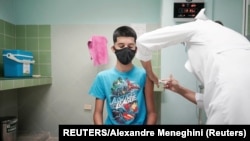

Esta semana las autoridades sanitarias en la isla anunciaron que comenzarán a vacunar a los adolescentes y a los niños para mediados de septiembre como parte de una campaña para inmunizar a más del 90% de la población para diciembre.

Los menores entre los 2 y 18 años recibirán al menos dos dosis de la vacuna Soberana-2 a partir del 3 de septiembre.